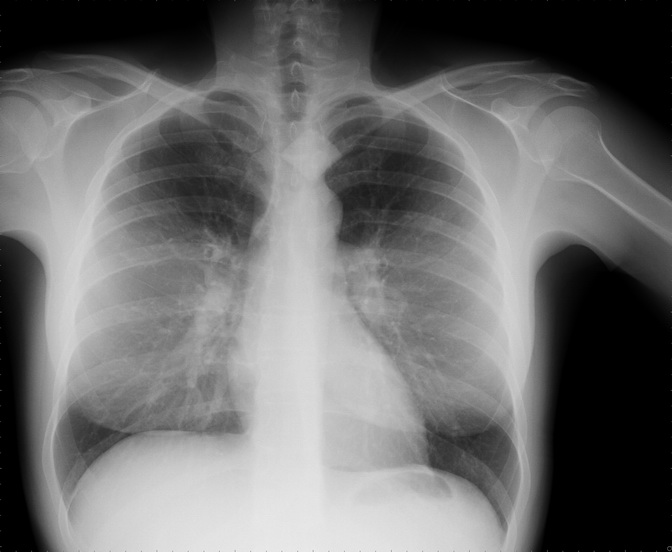

Medical Imaging

The main line of research of our team is Image Quality Assesment in Radiology. We are developing several tools and methods to obtain useful and objective indexes and procedures we can use to improve the performance of the radiology systems.